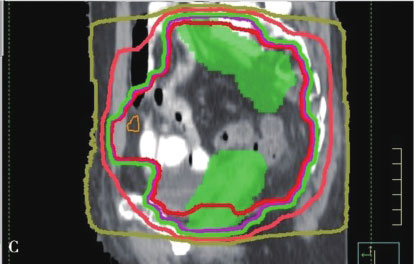

IMRT则是在3DCRT基础上的进一步发展,自1990年代早期IMRT被应用于临床以来,目前已成为一项常规开展的技术。IMRT通过多角度射野设置、多子野分割、滑窗等技术使均匀输出的通量分布变成不均匀分布,明显增加了靶区的剂量适形性,以避免或减少正常组织的照射,最大限度地限制治疗的副作用。IMRT的主要优势是其对凹凸靶区的适形能力,特别是凹面邻近重要器官时尤有优势。据估计,临床治疗的PTV有30%是凹形的靶区,因此可以从IMRT明显获益。另一方面,IMRT治疗方案是在治疗计划系统内通过逆向治疗计划的设计而得到,可以获得较正向计划方法更优的靶区适形性和更窄的侧向半影。通过调节每个射野的通量强度,在肿瘤靶区和正常器官之间形成一个很窄的剂量梯度,通常允许至少95%的PTV接受规定的处方剂量,同时保证周围正常组织的受量在既定的耐受范围之内。图7-2-1为IMRT与3DCRT技术的剂量分布图,其中图A、B、C所示为3DCRT剂量分布,图D、E、F所示为IMRT剂量分布,其中IMRT的剂量靶区适形性明显优于3D-CRT。

图7-2-1 IMRT与3DCRT技术的剂量分布图

A~C.为3DCRT剂量分布;D~F.为IMRT剂量分布